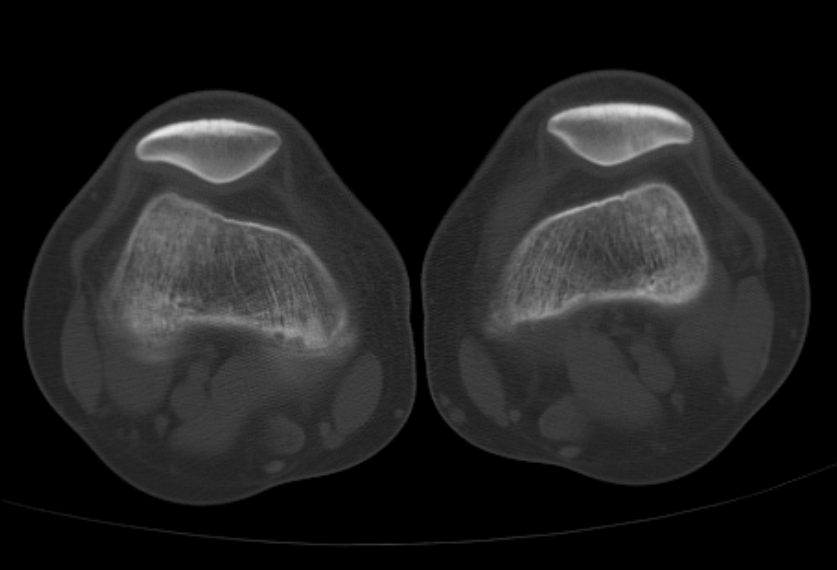

AO干货分享:

看胫骨平台是否平整的透视体位

现畸形、疼痛伴活动受限来院

复位满意,力线纠正